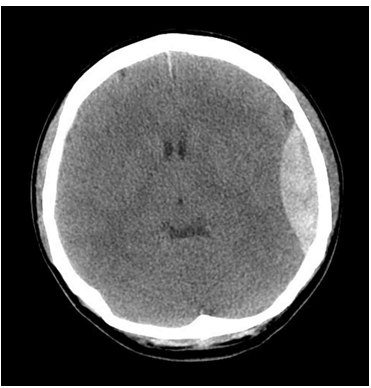

30세 여자가 3시간 전에 계단에서 미끄러져 벽에 머리를 부딪힌 후 머리가 아파서 응급실에 왔다. 혈압 130/95 mmHg, 맥박 83회/분, 호흡 18회/분, 체온 36.7℃이다. 의식은 기면상태(drowsiness)이고 왼쪽 두피가 부어있다. 사지마비는 없다. 혈액검사 결과는 다음과 같다. 뇌 컴퓨터단층촬영사진이다. 치료는?

CT: Epidural hemorrhage

Imp: 경막외혈종(epidural hematoma, EDH)

두부 외상 후 CT상 볼록렌즈 모양의 고음영 덩이가 보이기 때문에 EDH로 진단하고 치료를 위해 머리뼈절개술(craniotomy)을 시행한다.

• 두부 외상을 평가하기 위해 즉각적으로 Brain CT를 촬영하였고 Brain CT 상 볼록렌즈 모양의 고음영 덩이가 보이기 때문에 EDH로 진단한다.

• 의식은 기면 상태(drowsiness)로 저하되었으며 지속적인 두통을 호소하므로 두개내압이 증가를 의심할 수 있으며 Brain CT상 EDH의 크기가 크므로 수술적 치료를 시행한다.

• EDH의 수술적 치료는 머리뼈절개술(craniotomy)이다.